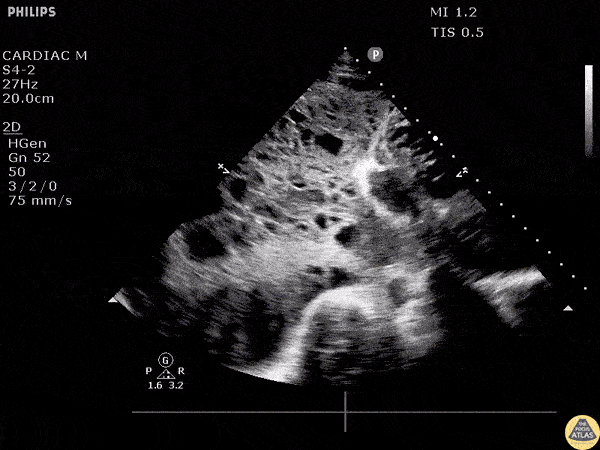

A patient with a history of lung cancer presented to the ED with a fever and hypotension. Subcostal window revealed a septated large malignant pleural effusion. Image courtesy of Robert Jones DO, FACEP @RJonesSonoEM Director, Emergency Ultrasound; MetroHealth Medical Center; Professor, Case Western Reserve Medical School, Cleveland, OH View his original post here